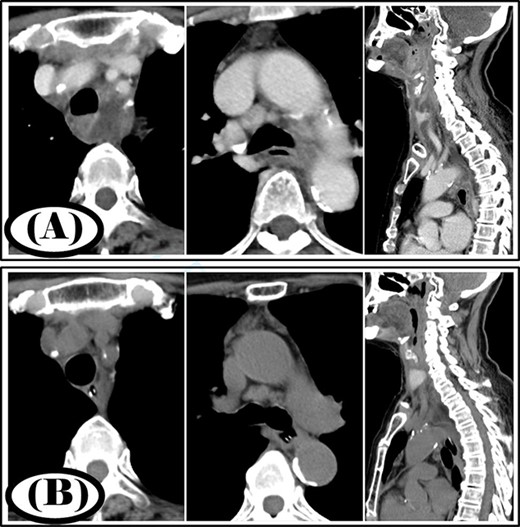

A 35-year-old man was diagnosed with a cervical abscess and initially underwent cervical drainage. The next day, he developed upper gastrointestinal perforation that was covered with an omental patch in a laparoscopic procedure. The cervical abscess did not improve and chest CT revealed that the infection had developed into the mediastinum (Fig. 2A). The patient was diagnosed with type II DNM and underwent mediastinal drainage using a cervical approach 3 days later. Initial antibiotic therapy consisted of meropenem at 9 g/day for 6 days as broad-spectrum antibiotic therapy. After Streptococcus anginosus group was detected in the mediastinal abscess cavity, the antibiotic was changed to ampicillin/sulbactam 12 g/day and was administered via intravenous infusion for 15 days. Continuous irrigation with saline (2 L/day) was initiated immediately post-surgery; however, 500 ml per day of saline was used for irrigation on the first 4 days. The duration of irrigation, drainage and hospital stay were 4, 16 and 39 days, respectively. Five weeks post-surgery, cervicothoracic CT showed no abscess cavity and an improvement in infection (Fig. 2B).

Case 2: pre- and post-treatment cervicothoracic CT; (A) pre-operative cervicothoracic CT and (B) cervicothoracic CT 5 weeks after treatment.